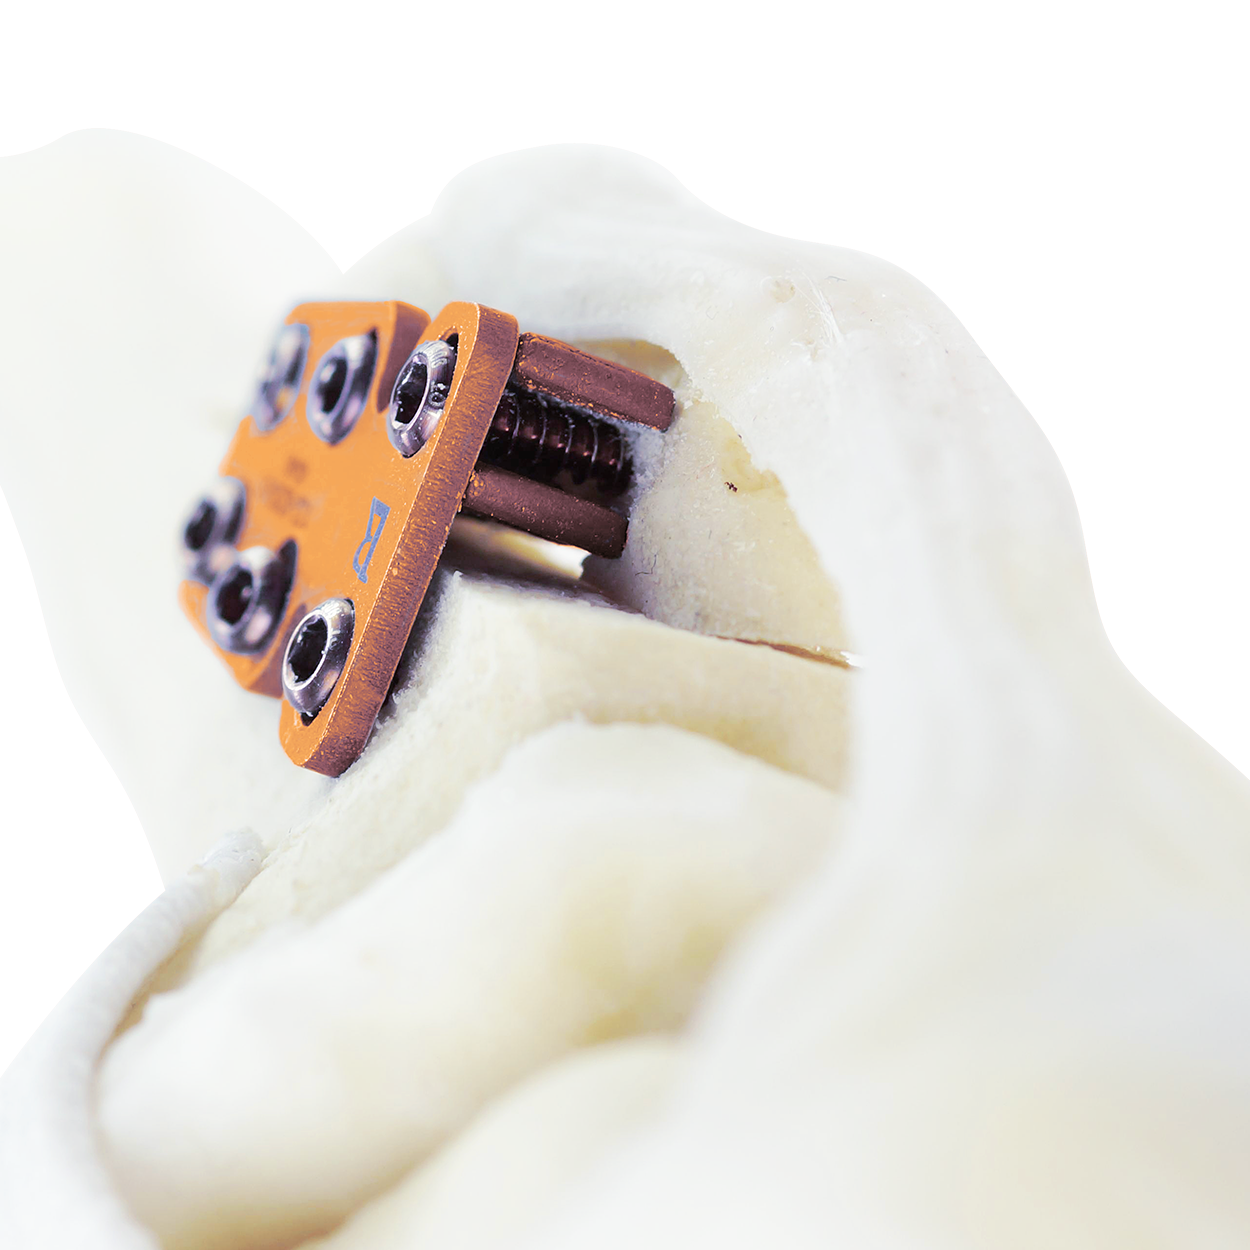

The design of the system ensures secure implant fixation for rapid bone growth and healing. It also allows for a recorrection of any alignment issues post-operatively, underscoring the patient-centric nature of the technique.

Designed to fit together seamlessly, the RAPID Luxation Plate and Spacer are securely fixed together to the bone by screws, preventing unwanted movement and ensuring stability and alignment of the patella within the trochlear groove. This allows for uninterrupted bone growth and integration, facilitating a rapid recovery process.

Compatible with TTA RAPID®

The RAPID LUXATION system is fully compatible with the TTA RAPID® system, allowing for seamless integration in complex cases involving both cruciate ligament rupture and concomitant patella luxation.

The compatibility stems from the shared instrumentation, including sawguides and tibia tappets, as well as the utilization of identical screws and patella spacers in both techniques. This compatibility not only streamlines inventory management but also leads to cost savings while expanding the range of services offered to patients. By leveraging these synergies, veterinarians can provide comprehensive care with enhanced efficiency and effectiveness.